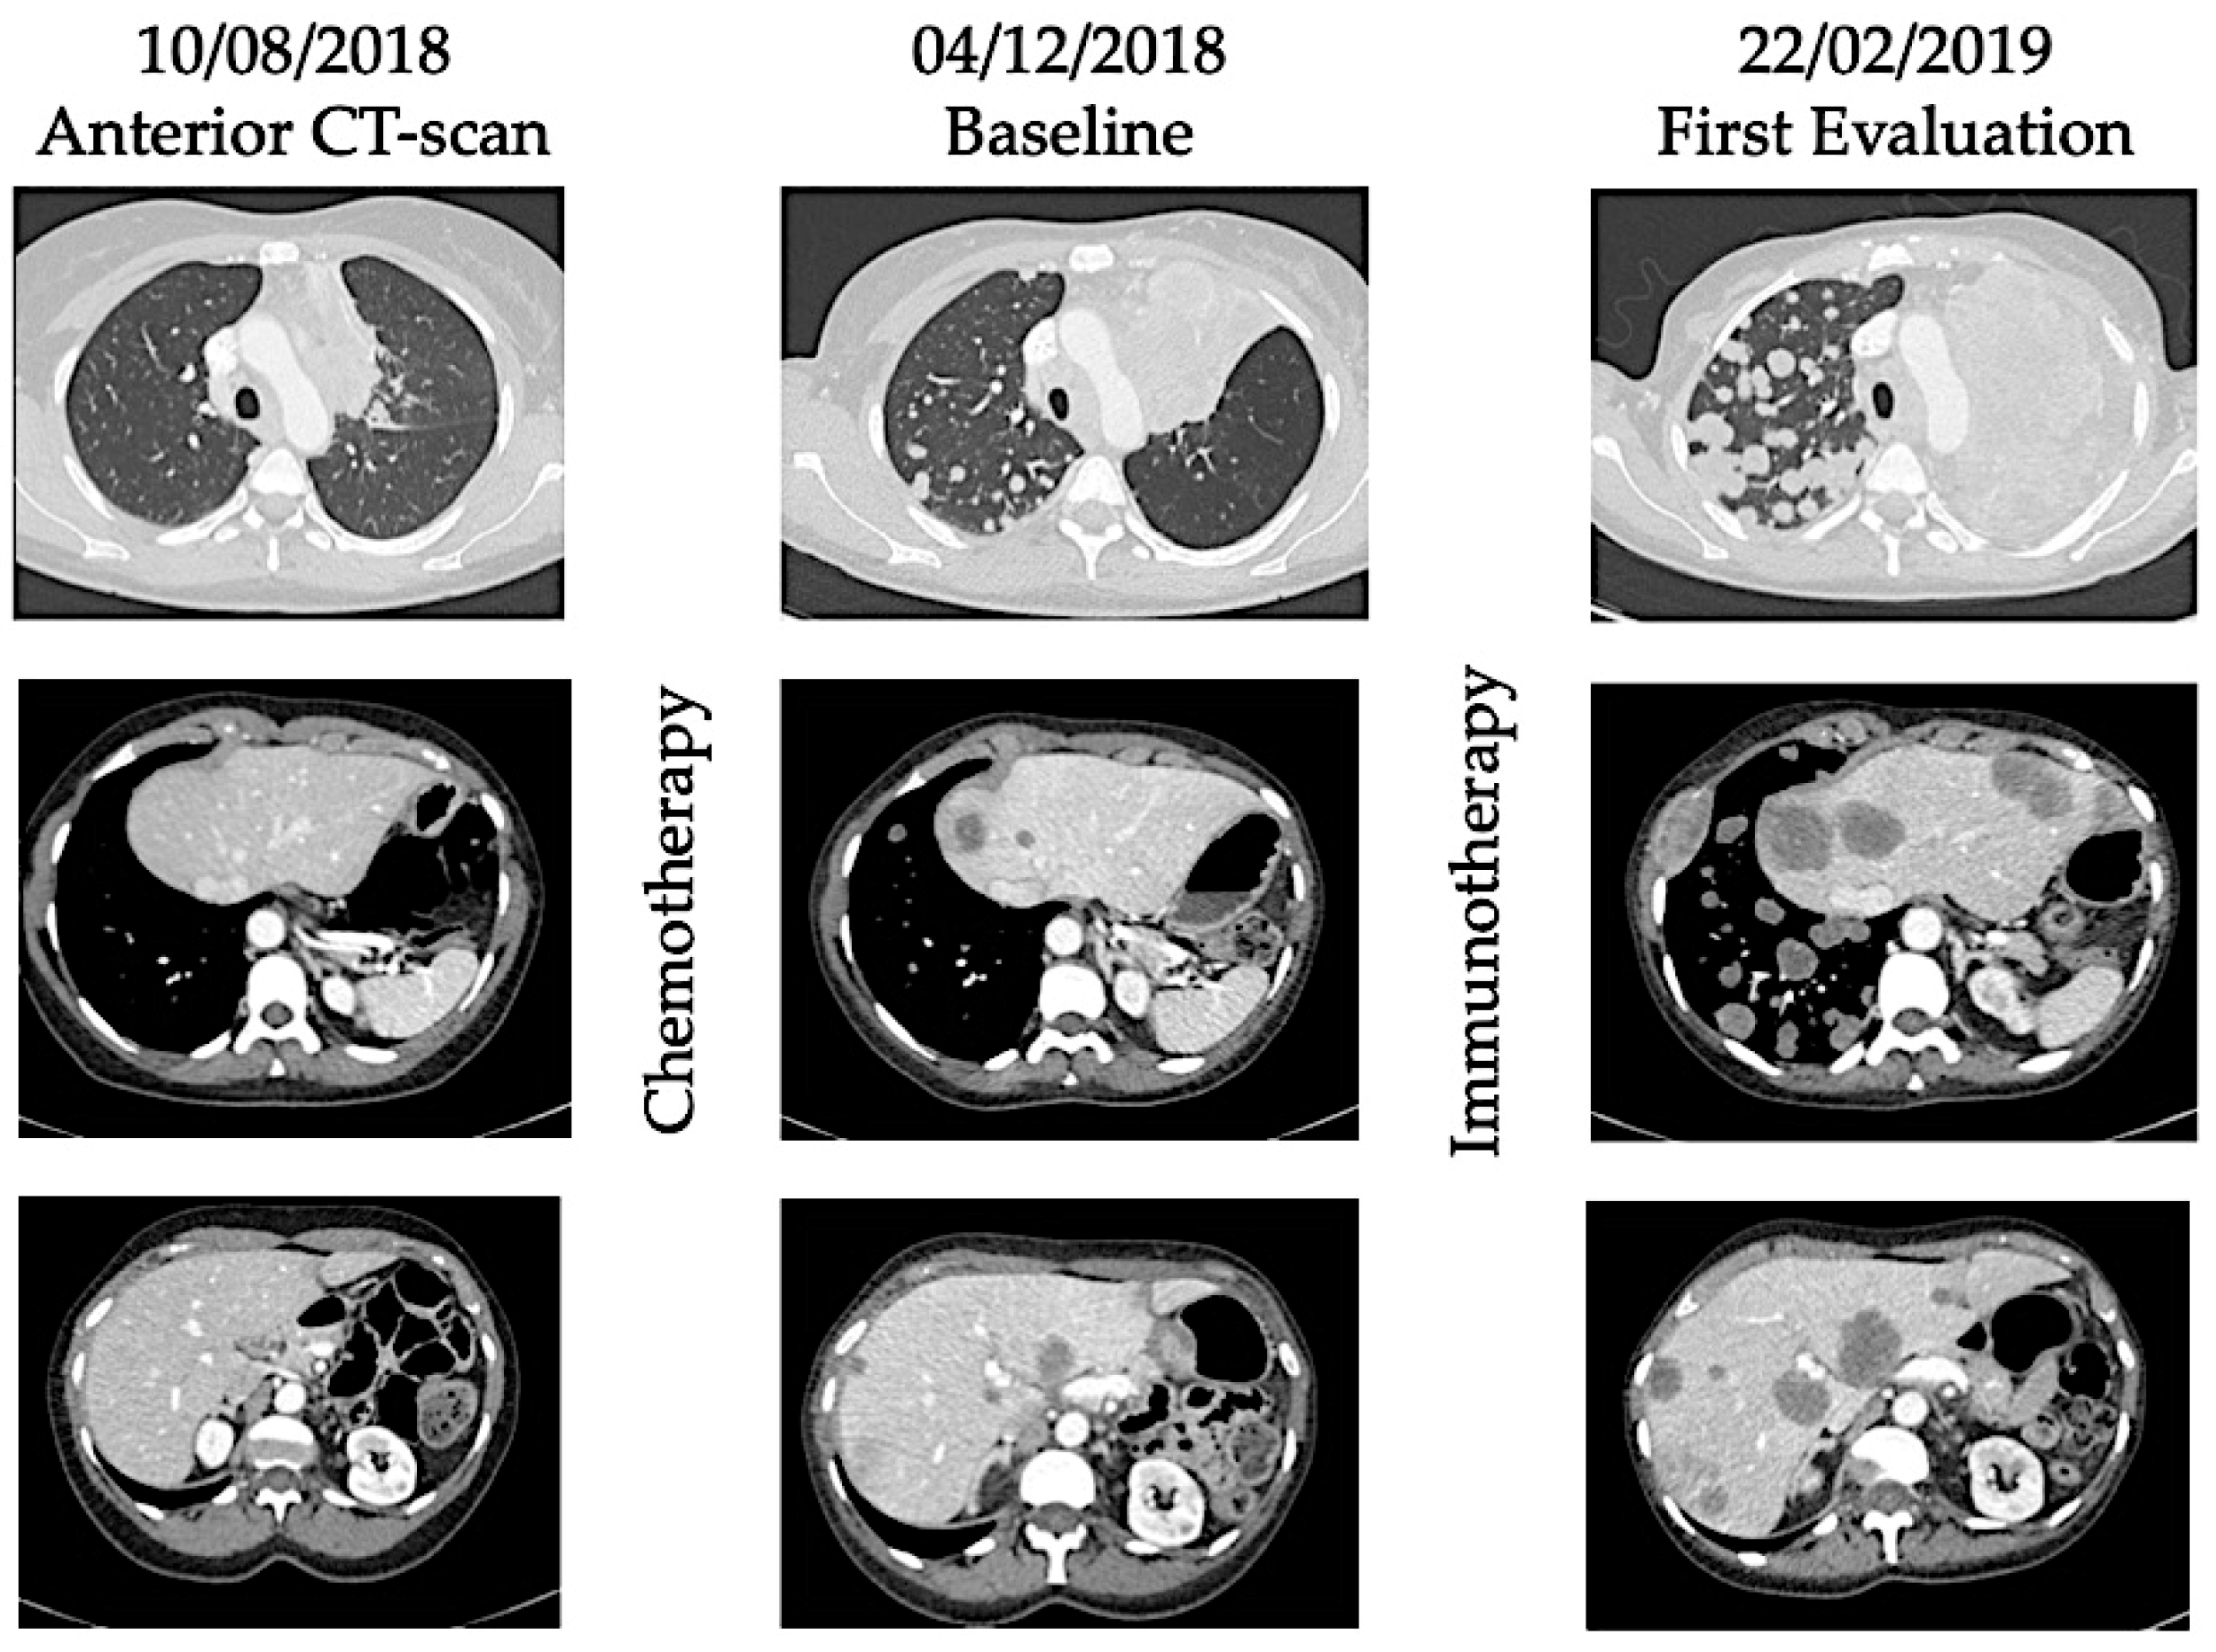

Hyperprogression was first described in case reports and retrospective studies of patients treated with ICI, with the observation that some cancer patients seem to have accelerated tumor growth after initiation of immunotherapy [14,16]. These data were consistent with OS curves from randomized trials, in which OS were better with chemotherapy than immunotherapy in the first weeks/months of treatment and then curves crossed, suggesting that ICI did worse than chemotherapy in a subgroup of patients [4,17]. See Figure 1 and Figure 2 illustrating the phenomenon of hyperprogression.

Figure 1. Examples of new patterns of response and progression with immunotherapy.

Figure 2. Illustration of hyperprogression under immunotherapy. A 53-year-old female patient with metastatic (lung) submandibular gland epidermoid carcinoma was treated in third line with weekly Methotrexate. After 4 months, patient experienced disease progression with appearance of lung, hepatic, and bone metastases. As fourth line, she received Nivolumab, an anti-PD-1 inhibitor. After 4 injections, she presented with major dyspnea with massive disease progression on computed-tomography (CT) scan. She died 64 days after immunotherapy initiation.